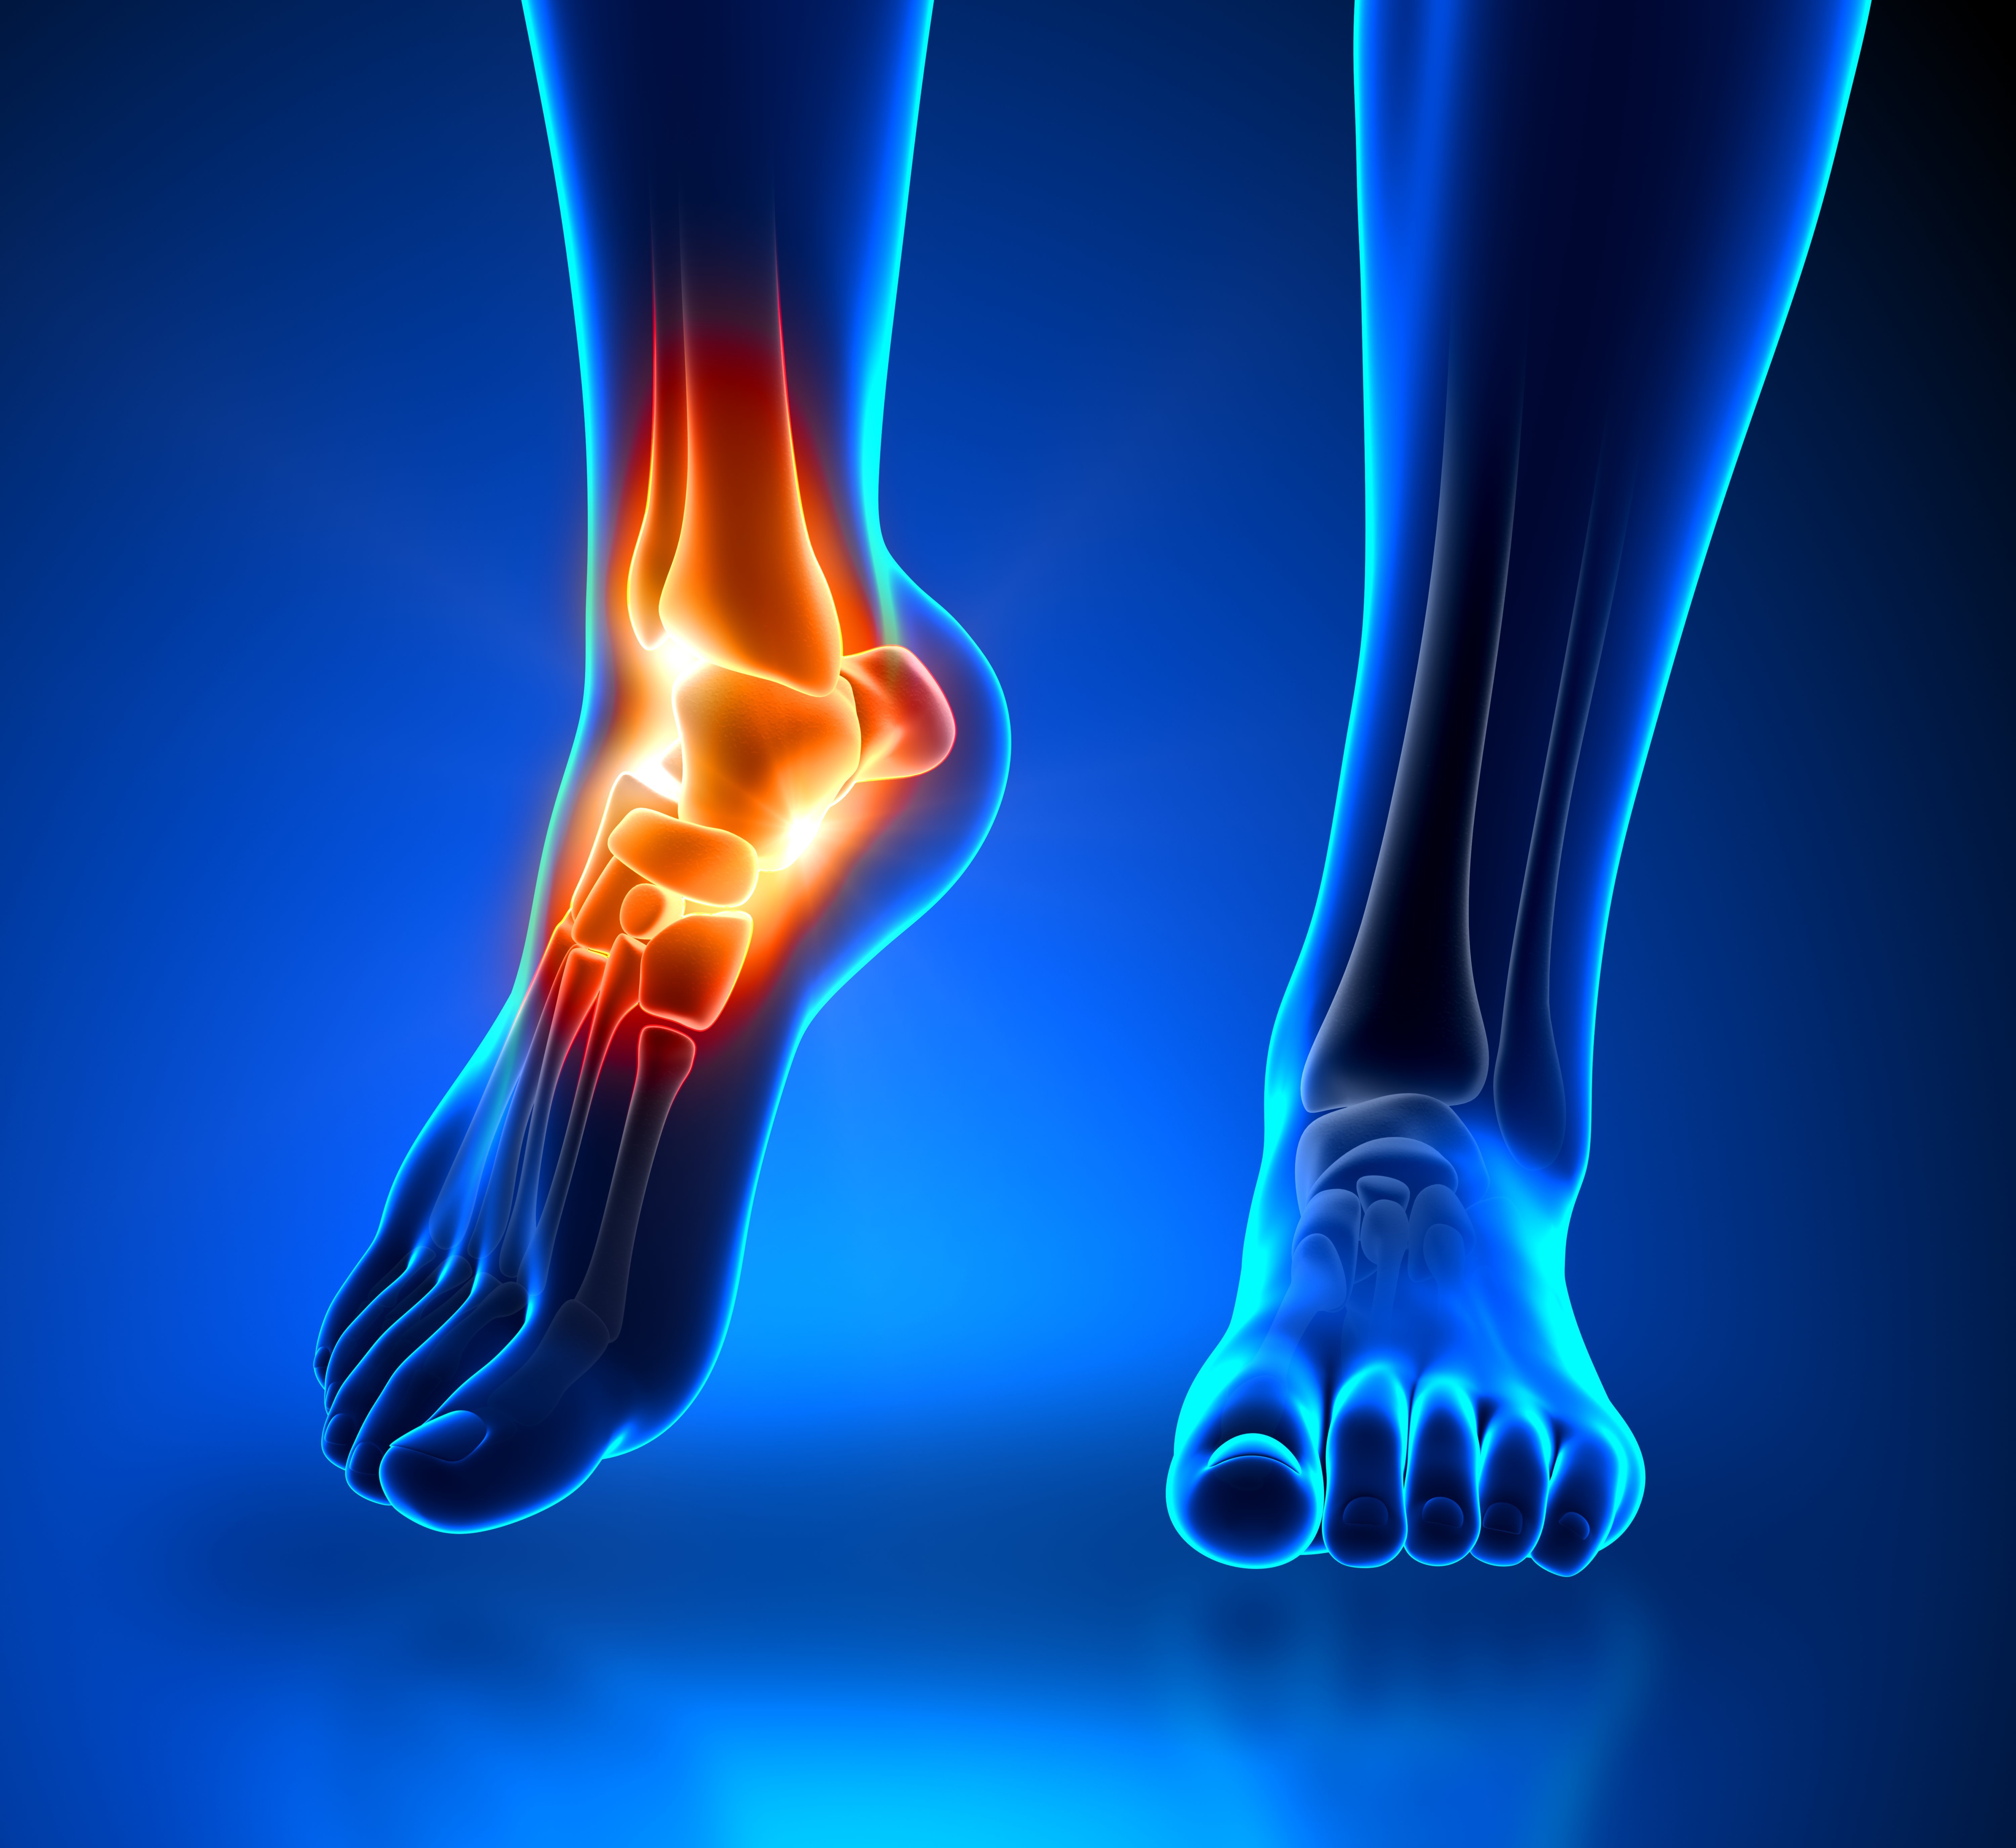

Η ταρσιαία αύλακα είναι μια περιοχή που βρίσκεται στην έσω και πίσω πλευρά του αστραγάλου. Περικλείει αρτηρίες, φλέβες, τένοντες και νεύρα που τροφοδοτούν το πόδι. Η αύλακα οριοθετείται από τα οστά και τους υπερκείμενους ινώδεις ιστούς. Μέσα από αυτή περνάει το οπίσθιο κνημιαίο νεύρο. Πίεση αυτού οδηγεί σε ανάπτυξη νευραλγίας, η οποία αναφέρεται ως οπίσθια κνημιαία νευραλγία ή σύνδρομο ταρσιαίου σωλήνα.